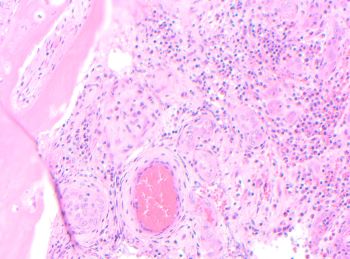

A 42-year-old female presents with nasal obstruction and a 3.0 cm polypoid nasal...

Case History